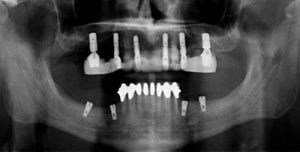

Traditional types of implants are Endosteal and Subperiosteal implants.[caption id="attachment_2794" align="alignright" width="300"]

Traditional implants[/caption]Endosteal implants are the more traditional type wherein a screw is fitted into your jawbone. After the healing period, the screw gets stabilized with a metal post and finally, a dental restoration is placed resembling the natural tooth.Subperiosteal implants are placed over the jawbone. These implants usually act as a support for making bridges or complete dentures. They are used in cases where bone resorption (bone height and bone density gets reduced) has taken place; that is when the bone is too weak to support an implant.